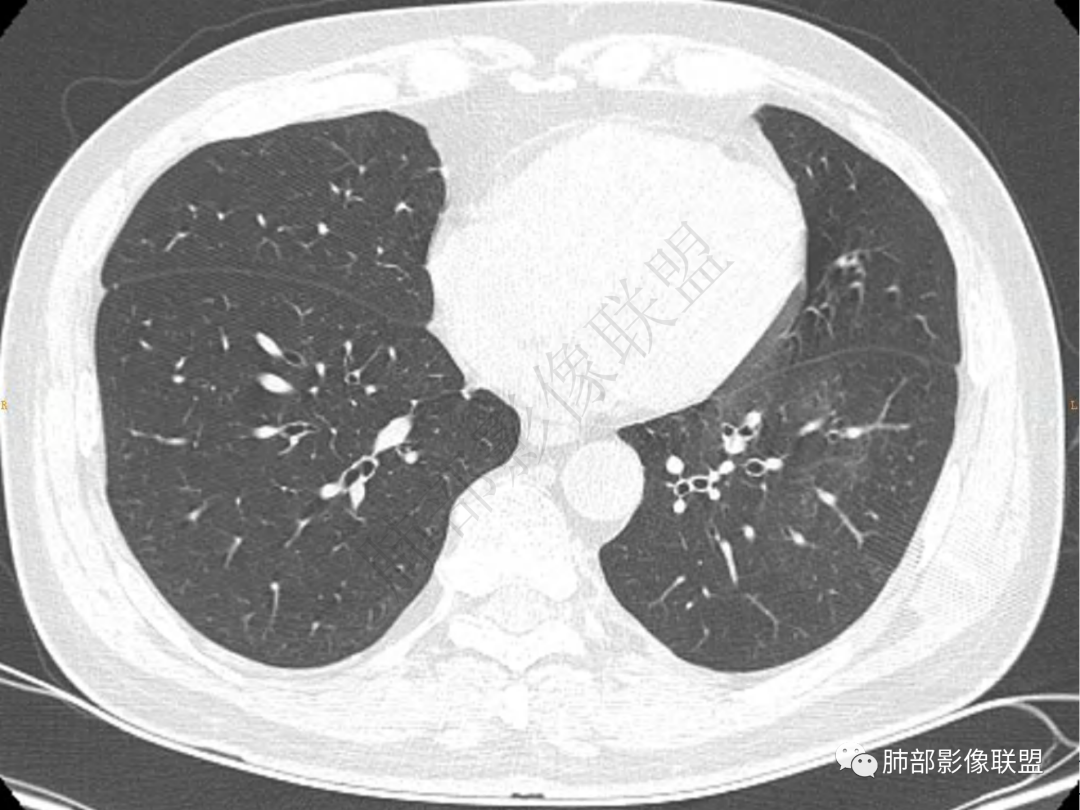

2.左肺下叶团片影,跨背段及内前基底段,实性部分类椭圆形,密度不甚均匀,可见毛刺及棘状突起,未见典型分叶及胸膜凹陷。病灶上下缘可见相应肺段支气管旁进侧出,管壁轻度增厚,未见狭窄阻塞。

3.周边较大范围磨玻璃影,边界相当模糊,小叶增厚明显。注意叶裂另一侧、左肺舌段亦可见磨玻璃影及增厚的小叶间隔。未见明确卫星病灶。

4.实性部分不均匀环形强化并显示一小范围低密度坏死区或空洞。较之肺窗,整体纵隔窗范围较小,提示病灶并不十分密实。抑或为不同时段图像。

5.双肺门及纵隔未见增大淋巴结。未见胸腔积液。